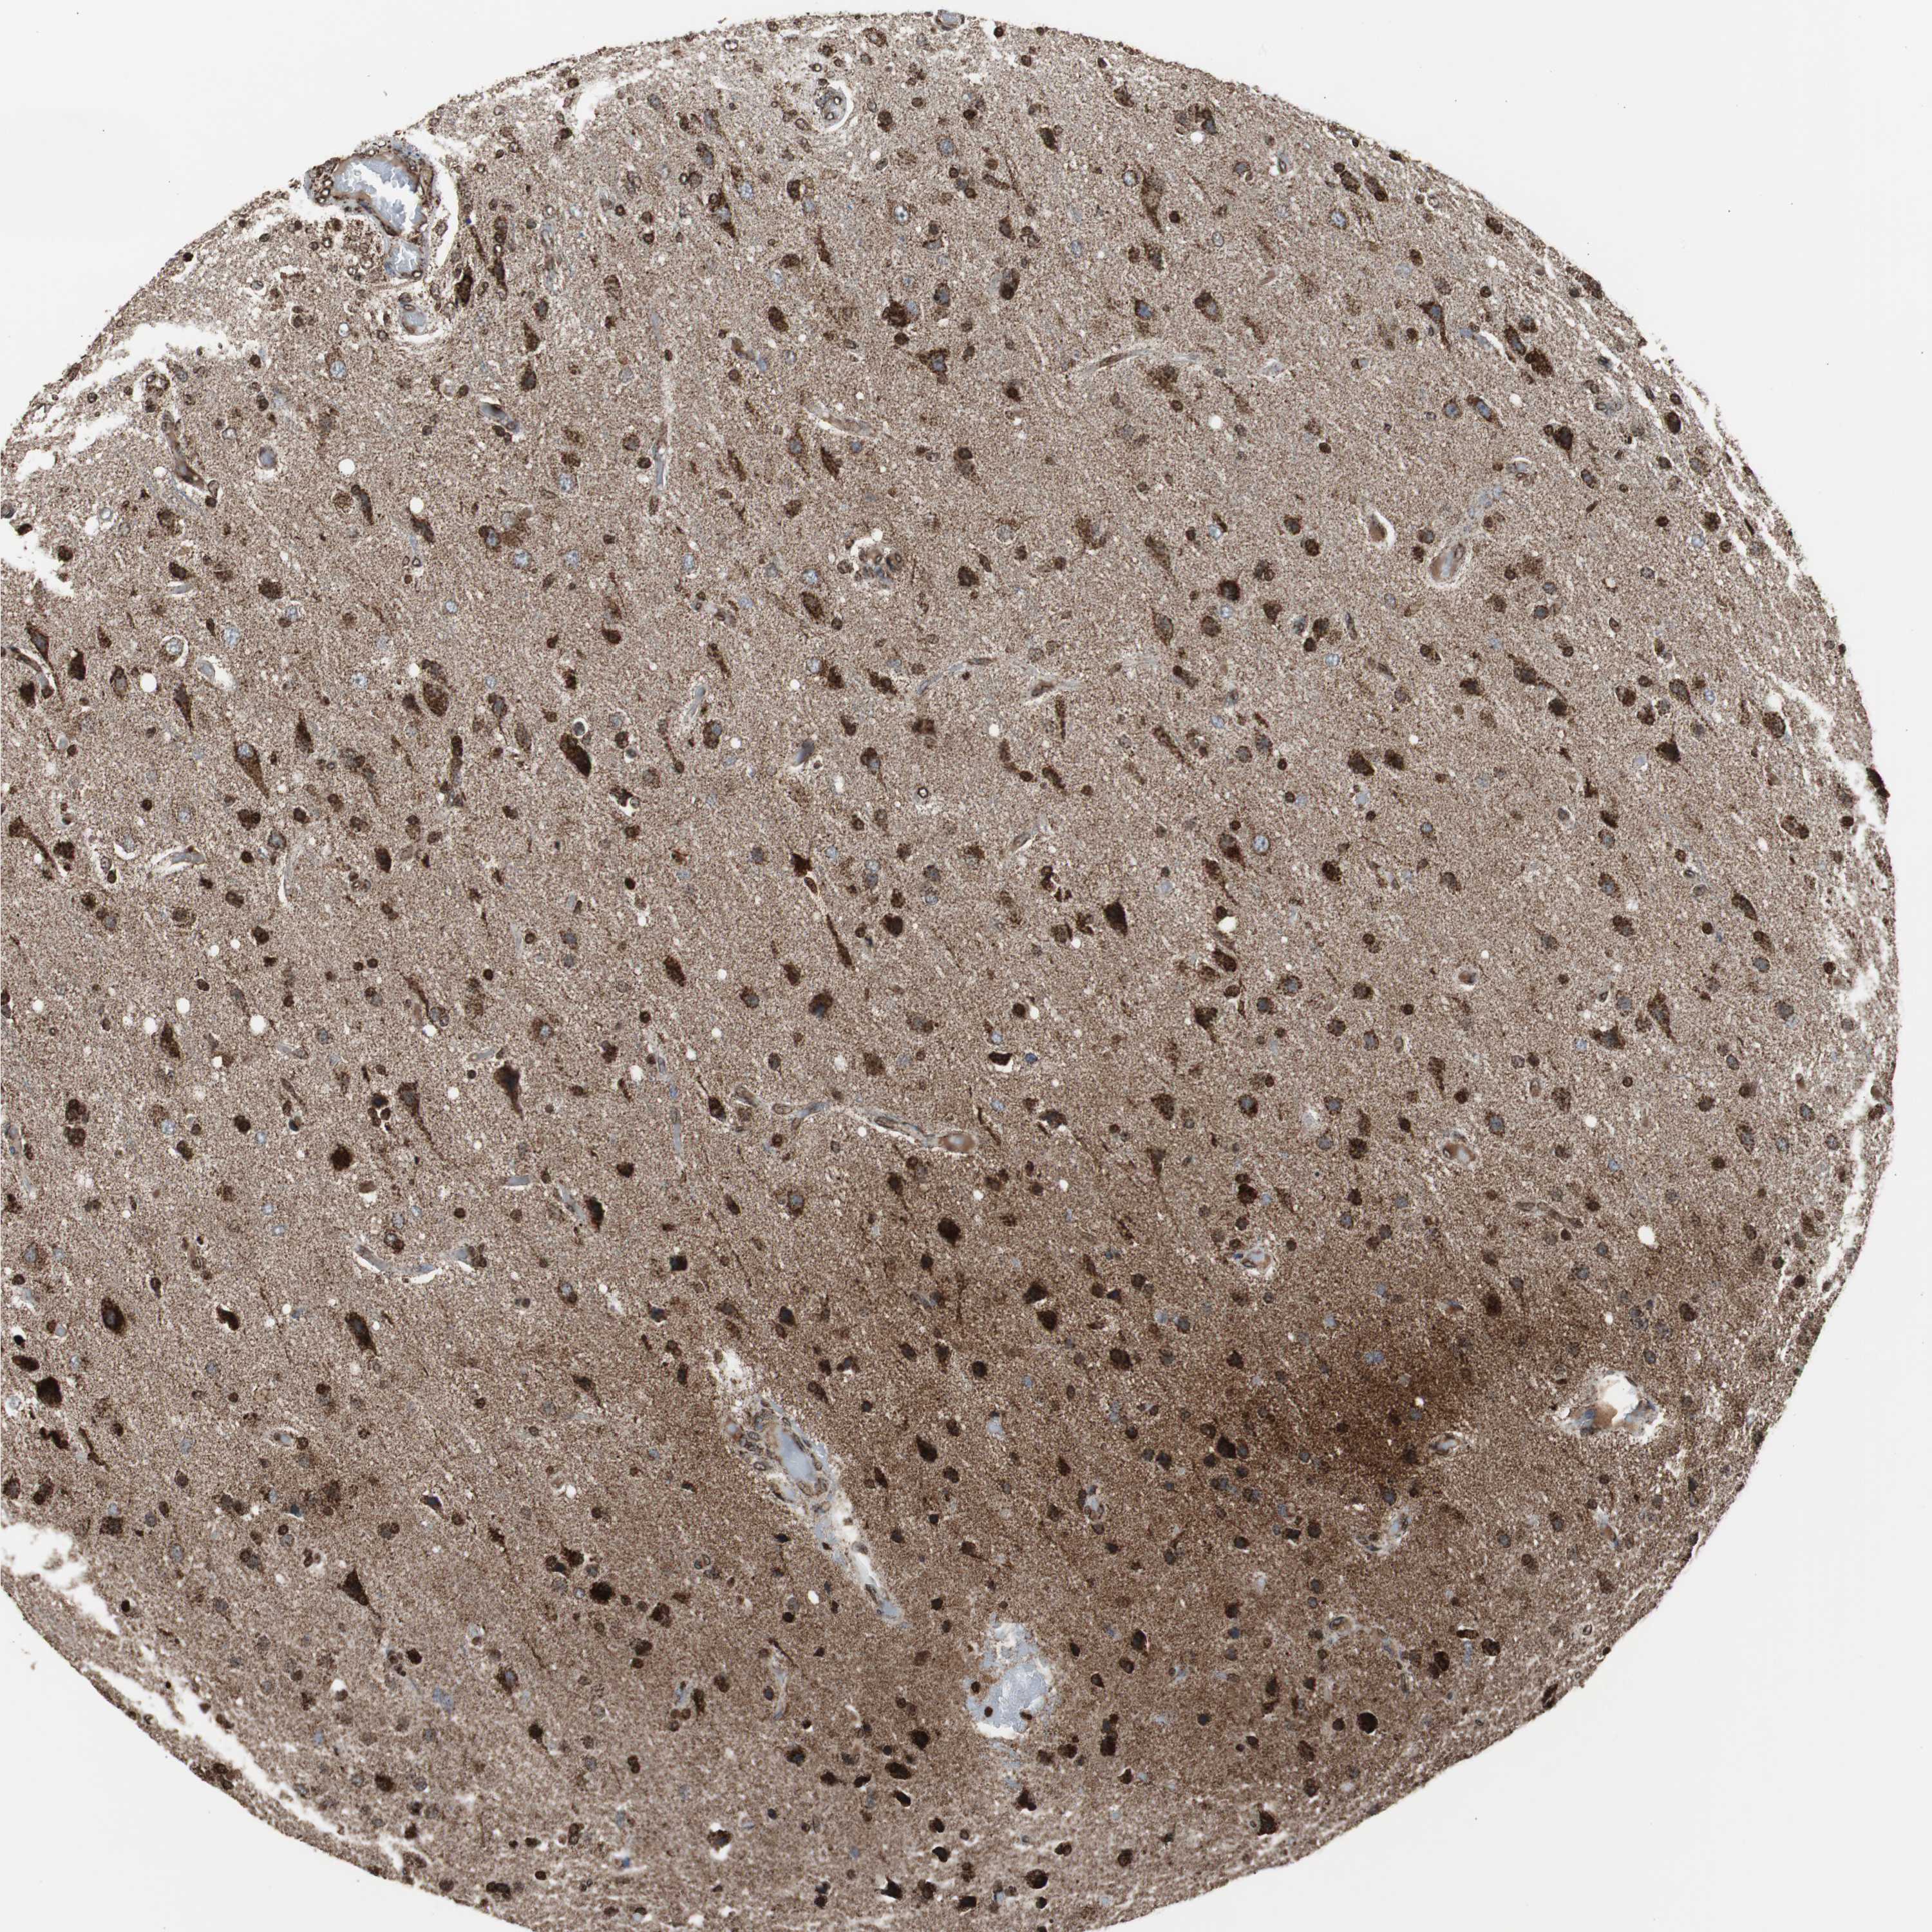

GLIOMA - Protein expressioni

A mouse-over function shows sample information and annotation data. Click on an image to view it in a full screen mode. Samples can be filtered based on level of antibody staining by selecting one or several of the following categories: high, medium, low and not detected. The assay and annotation is described here.

Note that samples used for immunohistochemistry by the Human Protein Atlas do not correspond to samples in the TCGA dataset.

Antibody stainingi

Antibody staining in the annotated cell types in the current human tissue is reported as not detected, low, medium, or high, based on conventional immunohistochemistry profiling in selected tissues. This score is based on the combination of the staining intensity and fraction of stained cells.

Each image is clickable and will lead to virtual microscopy that enables deeper exploration of all samples and also displays staining intensity scores, fraction scores and subcellular localization as well as patient and tissue information for each sample.

Antibody HPA000898

Antibody CAB005219

Staining

High

Medium

Low

Not detected

Intensity

Strong

Moderate

Weak

Negative

Quantity

>75%

75%-25%

<25%

None

Location

Nuclear

Cytoplasmic/membranous

Cytoplasmic/membranous,nuclear

Glioma, malignant, High grade

Glioma, malignant, Low grade